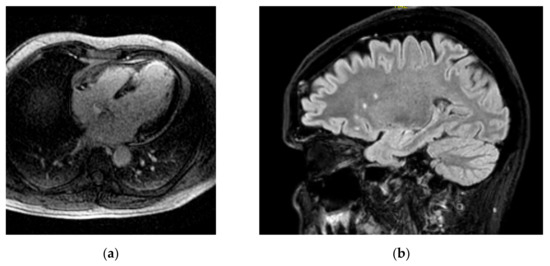

- Magnetic Resonance Imaging (MRI)

3.4. Cardiac Imaging in Heart Failure

- Echocardiography (ECHO)

- Cardiovascular Magnetic Resonance (CMR)

3.5. Role of the Proximal Aorta as a Coupling Device between Heart and Brain Perfusion